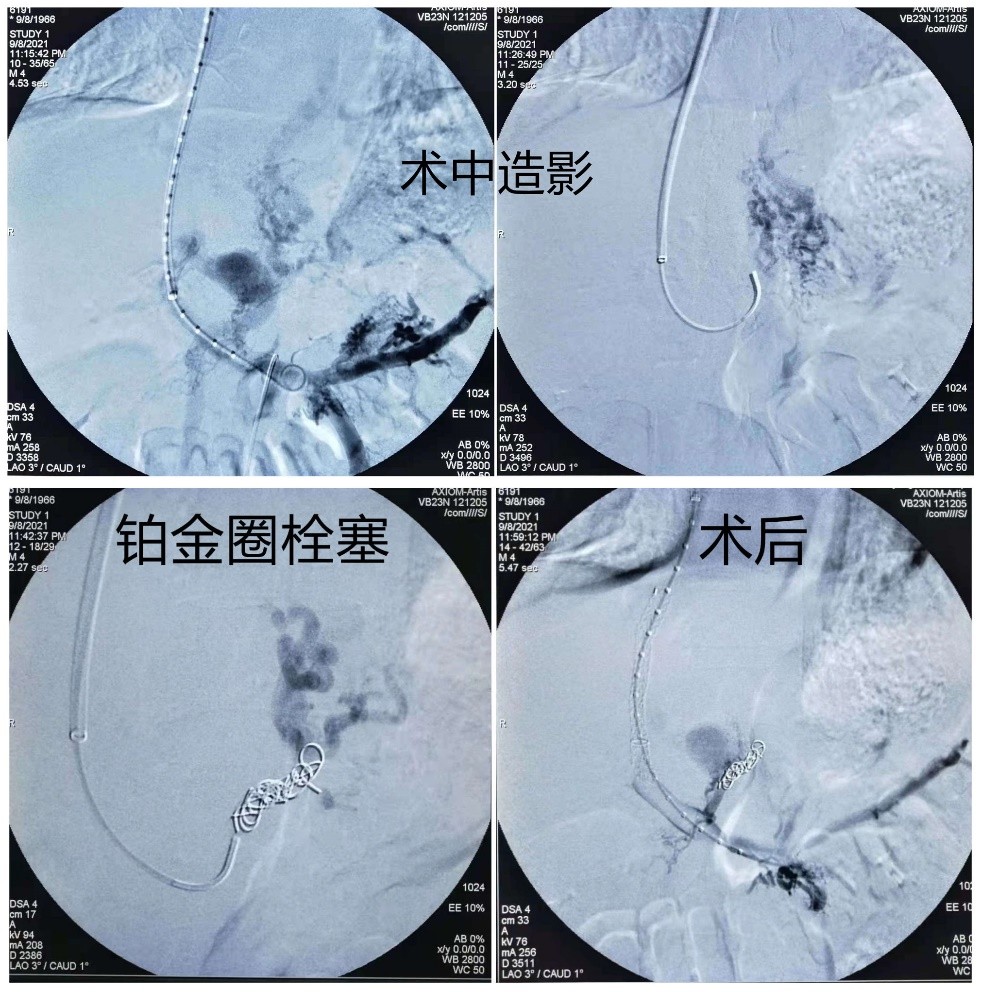

介入科团队针对患者病情认真讨论后,与家属进行了充分沟通,决定行TIPS手术。术中找到患者出血的胃底血管用带纤维的铂金圈进行栓塞,沿导丝引入TIPS覆膜支架系统释放支架,并用球囊反复扩张至凹迹消失,造影确认食道胃底静脉主干栓塞。手术最终取得圆满成功,术后患者生命体征平稳,意识清楚,并向在场的医护人员表达了衷心感谢。

据介入科主任张申众介绍,经颈静脉肝内门体静脉分流术(TIPS)是通过在肝静脉与门静脉之间的肝实质内建立分流道,以微创的方式,从结构上显著降低门静脉阻力,是降低肝硬化患者门静脉压力的关键措施之一。可有效减少食管胃静脉曲张再出血和腹水复发等肝硬化并发症,该手术是介入医生在DSA的透视监视下利用穿刺针、导管导丝等一系列器材对患者进行的微创治疗,手术时间短,不需开刀,患者手术全程清醒无痛苦,可谓是广大患者的康复福音。

TIPS手术涵盖了穿刺、造影、测压、球囊扩张、支架置入、血管栓塞等多项技术操作,其中在透视下由肝静脉向门静脉穿刺尤为困难,被认为是代表了外周介入的最高水平。因此,此次手术的成功实施,也标志着沈阳市第十人民医院的介入诊疗水平又迈上了一个崭新台阶,今后,医院还将再接再厉,继续强化肝硬化并门脉高压症的救治能力,竭尽所能守护百姓生命安全与身体健康。